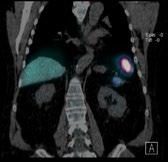

INTRODUCTION: Nuclear medicine imaging plays a pivotal role in evaluating complex prosthetic joint cases, particularly when conventional modalities are compromised by metal artifacts and nonspecific findings. This case study illustrates how the combined use of Gallium-67 scintigraphy and FDG PET imaging guided surgical intervention and evaluated disease progression with superior diagnostic sensitivity

CLINICAL PRESENTATION: A 61-year-old military veteran with a right total knee replacement presented with several months of knee swelling and severe pain. Initial evaluations including CT, bone scan, XR, ultrasound with fluid aspiration and MRI were inconclusive due to metallic artifacts and complex prosthetic fractures with adjacent oedema. The patient subsequently underwent Gallium-67 scintigraphy following an intravenous injection of 150 MBq Gallium-67 citrate, with imaging performed 48 hours later using a GE Discovery 670 system. The Gallium-67 scan demonstrated a significantly abnormal periprosthetic uptake, consistent with clinical concerns for infection. This result expediated surgical intervention and tissue biopsy of the affected area. The biopsy results revealed an extremely rare form of Diffuse Large B-cell Lymphoma involving the joint prosthesis. An FDG PET scan was then performed on a GE Omni PET system which revealed intense metabolic activity within the right knee and left knee, subcutaneous upper back activity and an FDG-avid right iliac fossa lymph node, suggesting systemic involvement. The patient underwent 6 cycles of R-CHOP and is awaiting further surgical intervention for the affected knee.

DISCUSSION: Prosthetic joint-associated lymphoma is an exceedingly rare phenomenon, with fewer than 20 cases documented in the global literature. The utility of 67Ga in lymphoma diagnosis is historically well demonstrated and this case underscores the complementary value of Gallium-67 scintigraphy and FDG PET imaging in complex prosthetic joint scenarios. While traditional imaging modalities were hampered by metal-induced artifacts and non-specific findings, nuclear medicine techniques facilitated the critical differentiation between infection and malignancy. This case also highlighted the importance of evaluating 67Ga-citrate imaging in complex clinical presentations with a comprehensive understanding of the mechanism of uptake in relevant pathologies The integrated imaging approach not only prompted surgical management but also informed systemic treatment planning, highlighting the evolving role of nuclear medicine in addressing challenging diagnostic dilemmas

Figure 1. 67Ga-citrate scan

Shimadzu Award